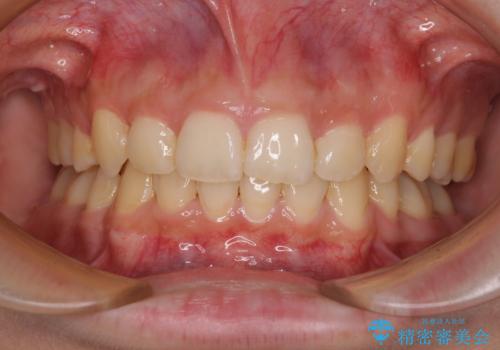

下顎前歯が隠れて突出した口元 ワイヤー装置での抜歯矯正

骨格的な左右差がありましたが、何とか当初予定していた期間で、左右対称の咬み合わせに仕上げることができました。

- 前歯のデコボコと口元の突出感を気にして来院された患者様です。

下顎骨の左右差や、上顎骨の前方位などが認められたため、上下左右の第1小臼歯4本を抜歯し、ワイヤー装置にて矯正治療を行うこととしました。